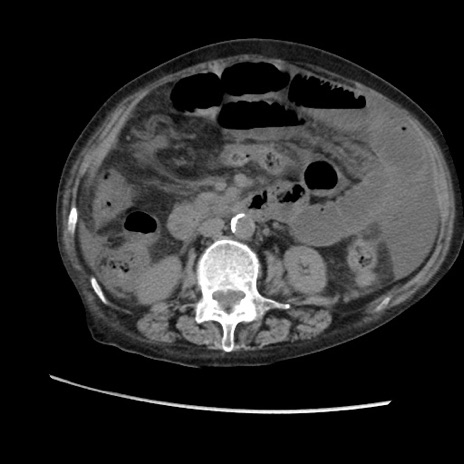

矢状断像

【症例】80歳代 女性

【主訴】腹部膨満感

【現病歴】他院にて肝硬変にてフォロー中。1週間前から便秘、腹部膨満感、臍部腫瘤あり受診となる。

【既往歴】肝硬変

【身体所見】腹部膨隆あり、皮膚変化なし、疼痛なし。

【データ】WBC 4600、CRP 0.25